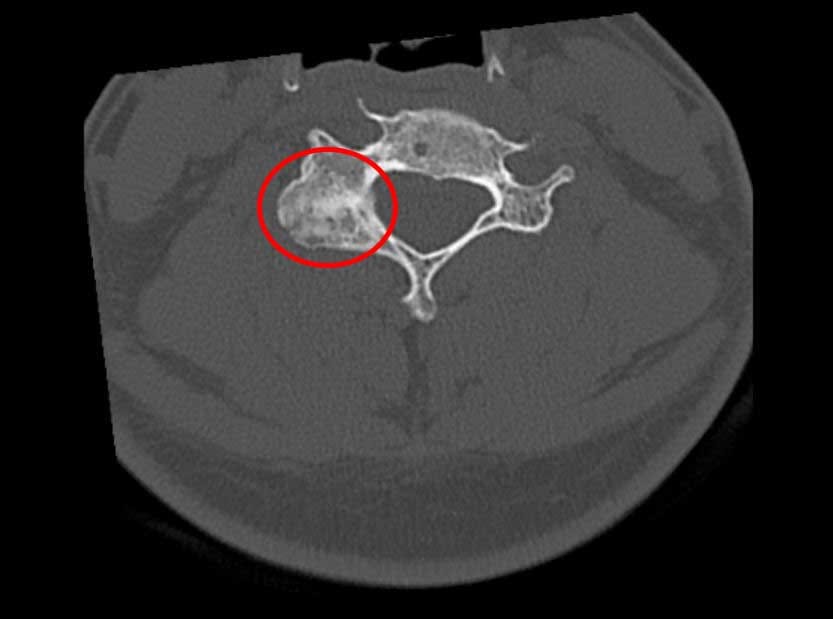

On 17th January 2020 Philip broke his neck playing rugby, couldn't afford the surgery and put faith in his body's ability to heal naturally. 18 months later, and another set of scans, showed that new bone had grown around the break.